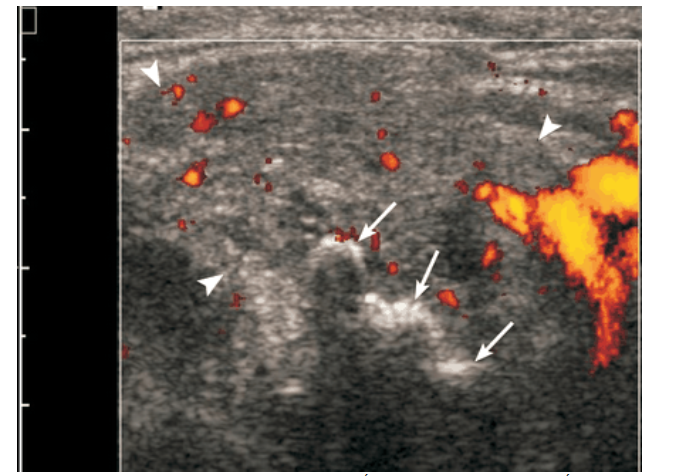

Viêm tuyến nước bọt mang tai cấp có thể hình thành áp-xe. Áp-xe tuyến nước bọt có biểu hiện sưng đau tuyến nước bọt có đỏ da, tuy nhiên khó phát hiện khi khám lâm sàng. Khi siêu âm, đặc trưng của áp xe tuyến nước bọt là tổn thương giảm âm hoặc trống âm có tăng âm phía sau, các bờ không rõ. Các chấm tăng âm do các bọt khí nhỏ có thể nhìn thấy bên trong ổ áp xe. Dịch hóa trung tâm có thể nhận ra dưới dạng một vùng vô mạch hoặc các mảnh lắng di động. Các ổ áp xe được tổ chức hóa có thể có một quầng tăng âm bao quanh.